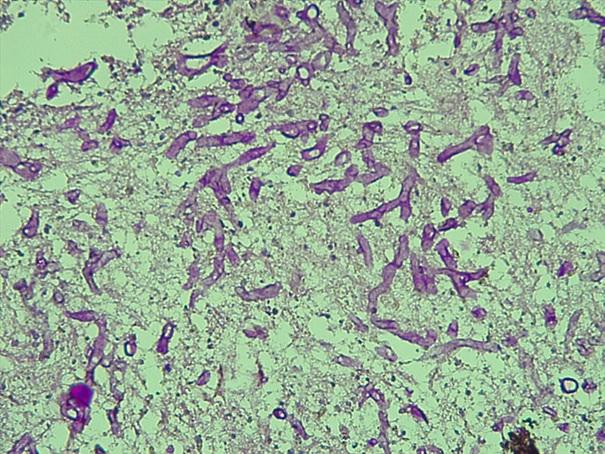

*Case 3 : Pr Modupeola Samaila/ Dr Rimamscep Ifusumu

email: mamak97@yahoo.com

Clinical detail: Female, 38 years. Orbital cystic tumour of 2 years duration.

Clinical diagnosis is orbital tumour query mucormycosis.

Please, consult the virtual slides of Case 3 below.